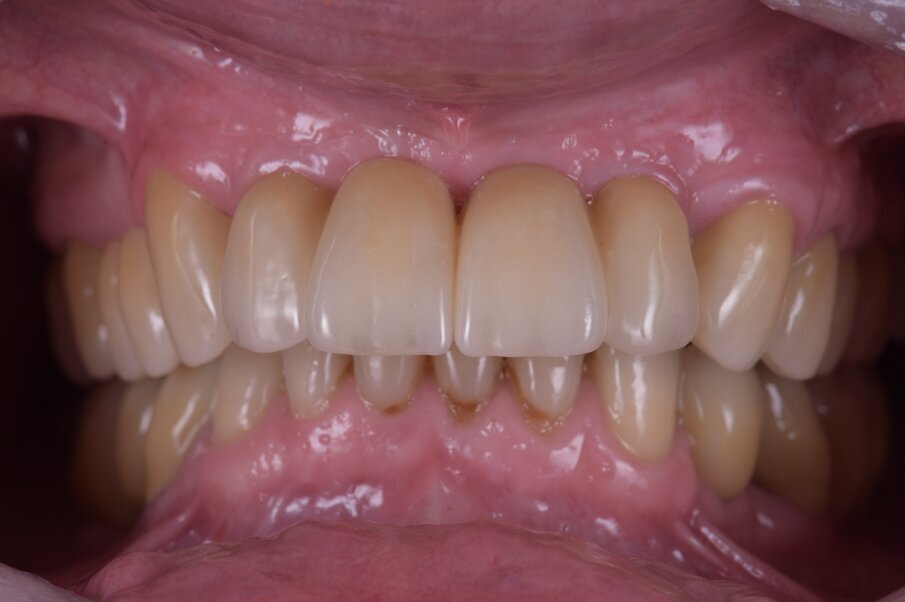

Il recupero funzionale ed estetico (Figg. 48, 49) rappresentano il traguardo dopo un lungo percorso. Il condizionamento della paziente ha rappresentato un ostacolo nelle libere scelte cliniche segnando di conseguenza l’intero percorso. L’aspetto psicologico ha giocato un ruolo importante nella realizzazione del piano di trattamento, la malattia precedente e il lungo periodo di provvisorizzazione ha arrecato nella paziente un forte disagio. Talvolta quest’aspetto induce il clinico a fare dei compromessi procedurali e anche noi abbiamo cercato di ottimizzare una riabilitazione estetico funzionale correndo dei rischi procedurali a fronte di una richiesta conservativa e talvolta riduttiva nelle procedure chirurgiche. A oggi il follow-up e i controlli di igiene e di verifica della funzione è cadenzato e rigorosamente rispettato dalla paziente. A 5 anni non sono stati evidenziati problemi dei materiali impiegati né tantomeno funzionali (Figg. 50, 51).

Il trattamento è durato 12 mesi. Non è stata anticipata alcuna procedura e abbiamo atteso i giusti tempi nella guarigione dei tessuti molli e duri attendendo sei mesi dall’inserimento dei due impianti in regione incisiva e dopo debito controllo radiografico. La giusta maturazione delle procedure attuate ha consentito una stabilità che ancora oggi a distanza di 5 anni rimane inalterata con piena soddisfazione personale. Inoltre la scolarizzazione della paziente nel mantenimento domiciliare ha creato un rapporto di benessere e di fiducia che reputiamo indispensabili nel follow-up a lungo termine. Non abbiamo riscontrato alcuna differenza significativa tra gli impianti in Zirconia e quelli in titanio dal punto di vista dei controlli radiografici e della qualità dei tessuti. In regione frontale l’estetica rosa è esaltata dalla trasparenza favorevole di collarini bianchi che non opacizzano la visione in trasparenza. Reputiamo l’approccio digitale come un forte ausilio tecnologico nelle scelte delle procedure e dei materiali oltre che un’eccellente strumento di comunicazione col paziente che contrariamente a noi è spesso disorientato verso le nostre procedure per il dubbio del risultato.